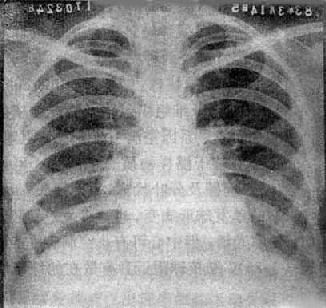

急性粟粒型肺结核

图3-1-22 急性粟粒型肺结核

两肺野布满粟粒状病灶,分布均匀,肺门大